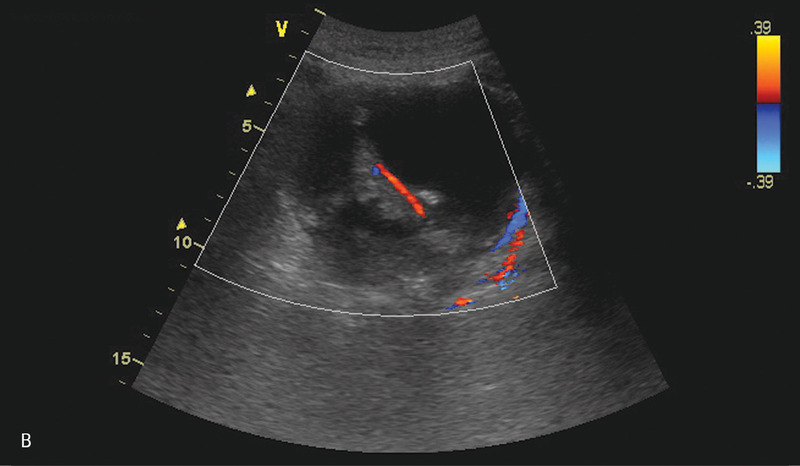

Po kolejnych 3 tygodniach nastąpiło nasilenie dolegliwości sugerujących zaostrzenie zapalenia (wymioty, bóle brzucha, wzdęcie). Pacjenta ponownie przyjęto na oddział chirurgiczny. Rozpoznanie nawrotu zapalenia potwierdzono w badania laboratoryjnych. Wykonano badanie USG, które wykazało obecność kilku zbiorników płynu w śródbrzuszu, w rzucie trzustki oraz po stronie lewej w nadbrzuszu i w lewej jamie opłucnowej (ryc. 2).

Rycina 2. Badanie USG jamy brzusznej. A. Przekrój poprzeczny przez nadbrzusze. Widoczny hipoechogeniczny zbiornik płynu w rzucie głowy trzustki, przesłonięty powierzchownie przez dwunastnicę. B. Przekrój podłużny przez nadbrzusze. Widoczny opisywany grubościenny zbiornik płynu w śródbrzuszu. W centralnej części widoczne zmiany otoczone płynem naczynia. C. Przekrój podłużny przez lewe podżebrze. Widoczne kolejne zbiorniki płynu w otoczeniu śledziony oraz w rzucie trzonu żołądka.